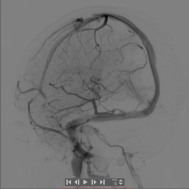

右侧大脑中动脉球囊扩张治疗前后对比图